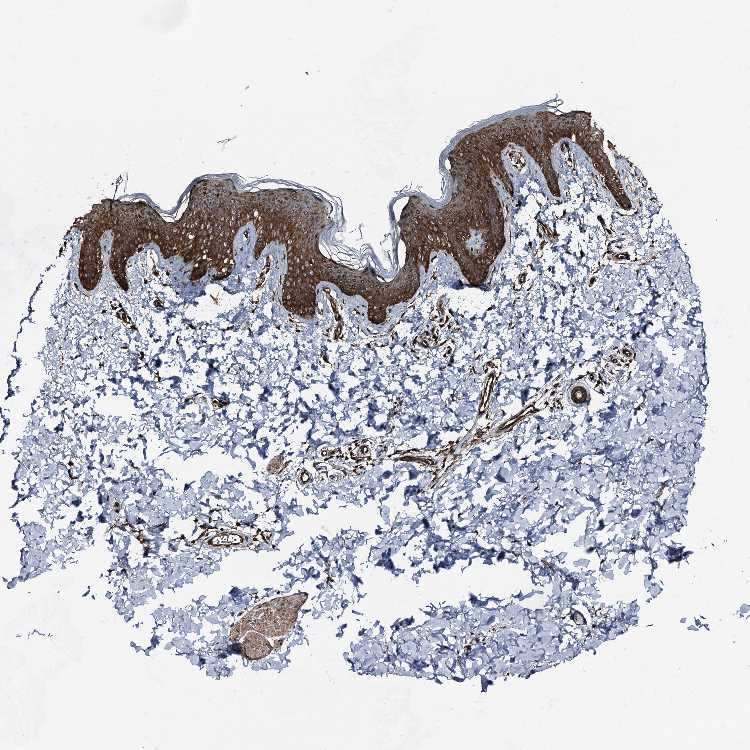

SKIN 2 - Antibody stainingi

Antibody staining in the annotated cell types in the current human tissue is reported as not detected, low, medium, or high, based on conventional immunohistochemistry profiling in selected tissues. This score is based on the combination of the staining intensity and fraction of stained cells.

Each image is clickable and will lead to virtual microscopy that enables deeper exploration of all samples and also displays staining intensity scores, fraction scores and subcellular localization as well as patient and tissue information for each sample.

Antibody HPA035116Antibody CAB010207

Cells in basal layer High-

Cells in corneal layer Not detected-

Cells in granular layer High-

Cells in spinous layer High-

Endothelial cells High-

Epidermal cells -Medium

Extracellular matrix Not detected-

Fibrohistiocytic cells High-

Langerhans cells High-

Lymphocytes High-

Melanocytes High-

Vascular mural cells High-